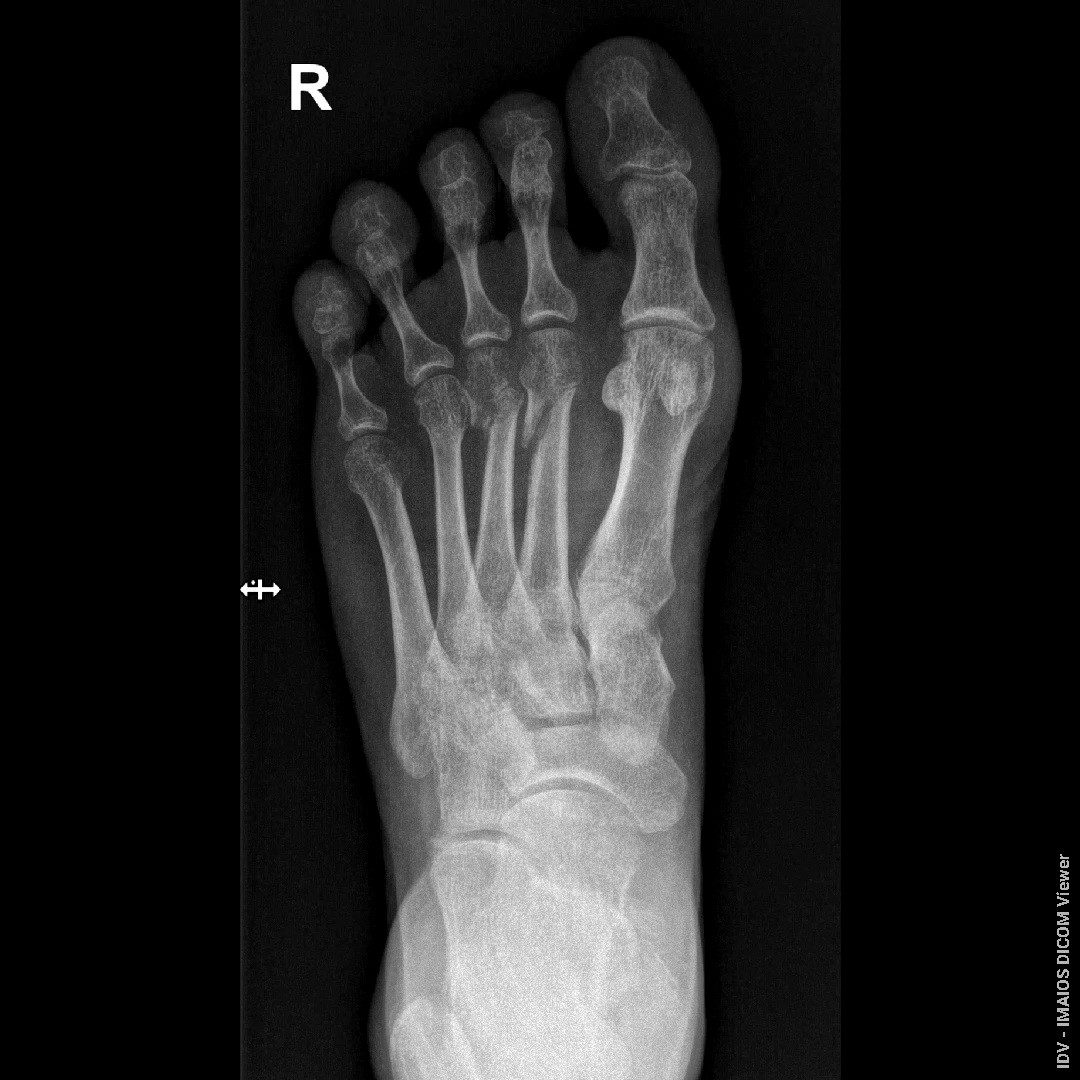

Здравствуйте, Доктор! Перелом был 23.06.2025. посмотрите пожалуйста снимки от 08.08.2025, срослись ли переломы, образовалась ли костная мазоль, можно ли начинать ходить?

Здравствуйте. По представленным снимкам видны признаки формирования костной мозоли в области перелома, что говорит о начале сращения однако линия перелома ещё прослеживается, и полное костное сращение скорее всего не завершено. Начинать ходить без опоры пока рано и нагрузку нужно увеличивать постепенно и только по разрешению лечащего травматолога после клинического осмотра и контрольного рентгена.